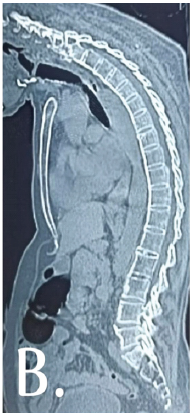

Deformity Correction in Ankylosing Spondylitis with Cervical Fracture: A Case Report

Jitendra Kumar Rout , Sumit Kaushik , Abhay Tyagi